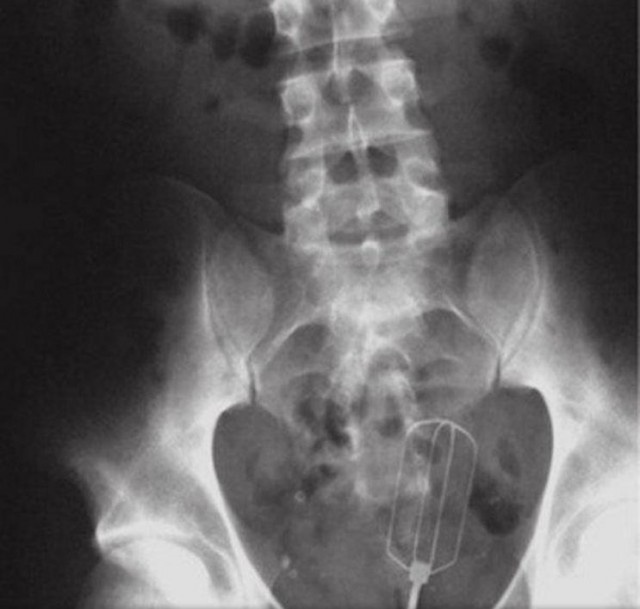

・泡だて器、何を泡立てたのかは謎